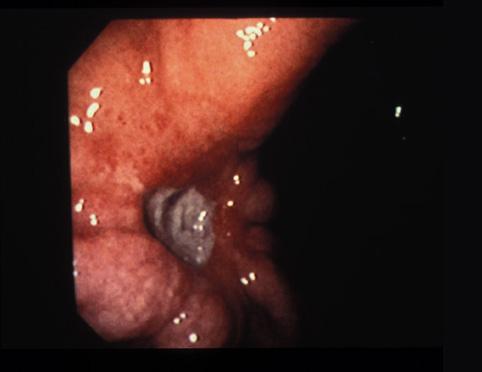

Criteria of Hist.ClassificationMalignant epithelial tumor/Signet-ring cellcarcinoma

LocationStomach/Angle

Technique, MethodEndoscopy

Macroscopic TypesType 0/IIc (IIc+III) Superficial depressed and excavated type

Size30 - 34

Depth of Tumor Invasionmucosa